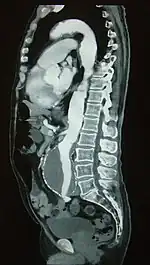

A ruptured AAA with an open arrow marking the aneurysm and the closed arrow marking the free blood in the abdomen Sagittal CT image of an AAA

Sagittal CT image of an AAA Biomechanical AAA rupture risk prediction